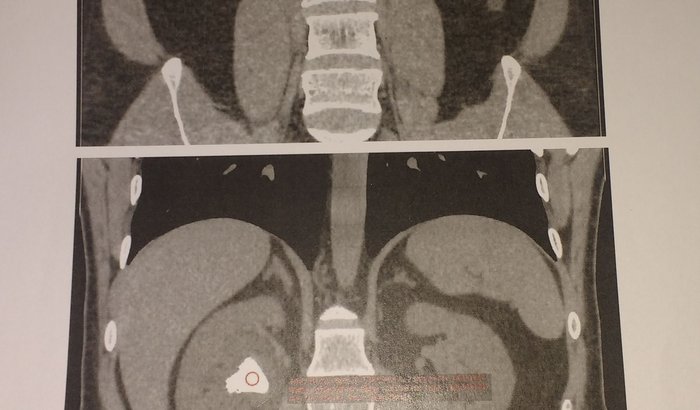

Cirurgia Litotripsia percutânea rim tem custo de $15 a $20 particular em nossa cidade... Estamos aguardando para Florianópolis, pois em nossa cidade Sus não cobre material, mas já estamos dois anos c este problema ée infelizmente já é insuportável... Por isso, mesmo constrangida, venho pedir ajuda...